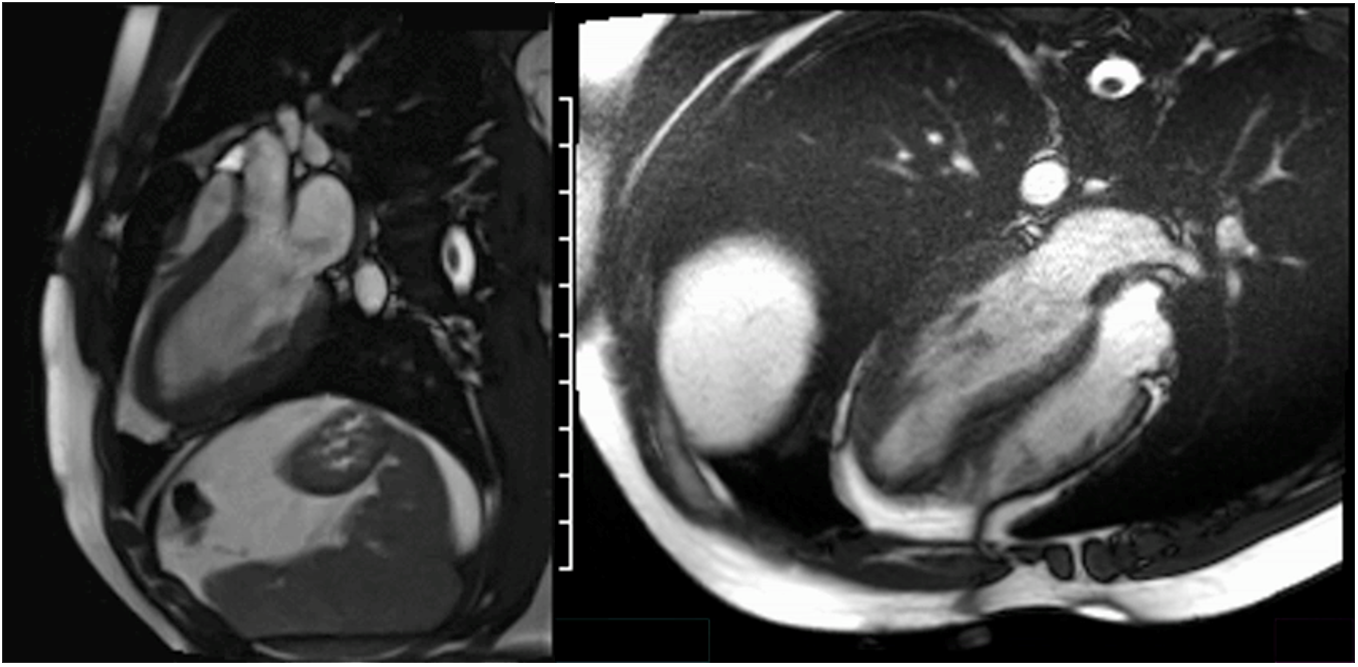

cMRI Findings

The cMRI had remarkable findings (Image 2):

- LV. Normal size with wall thickness 1.1 cm (anteroseptal and inferolateral); LVEF 59%, which is within normal range for an athlete (52-69%). No myocardial scar on postgadolinium imaging. Prominent apical insertion of the papillary muscles, a benign variation common in athletes.

- Extracellular volume (ECV). Measured at 23.2% in the apex and 25% in the basal septum, both within normal limits, suggesting physiological hypertrophy without significant myocardial fibrosis or pathology such as HCM.

- Right ventricle (RV). Normal size and function, RV ejection fraction 54% (>45%).

- Valvular findings. No significant valvular disease.

Image 2

The inclusion of the ECV measurements is particularly important in distinguishing between normal myocardial tissue and pathological changes. The normal ECV values suggest no significant myocardial fibrosis or abnormal myocardial tissue composition, further supporting the suspicion that the hypertrophy observed on echocardiogram was likely due to athletic training rather than HCM.